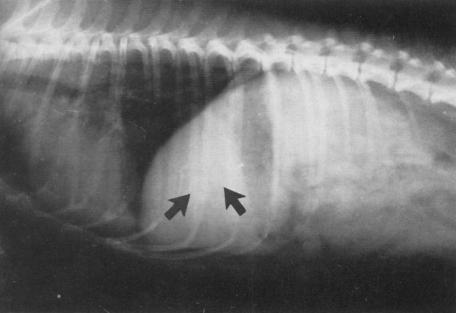

根据主人主诉小狗精神状态不佳,不吃食物,且伴有呕吐。病程已持续一个星期,排尿正常。已在其他医院就诊,服用胃肠炎药物治疗后不佳。在家里以米饭和肉食为主。但呕吐严重时,可看见呕吐物为液体状。经过兽医临床触诊后,发现小狗腹部有异常,口腔有异味,且牙齿周边布满大量牙垢。体温39.6°C,淋巴未见肿大。初步怀疑胰腺炎、胃肠异物,胆囊炎或胃炎。遂进一步X光线和超声检查后,观察到体内有两个胆囊结石,确诊为胆囊结石。

肝脏区域高密度点状阴影

X光片检查肝脏区域

X光线可见结石大小(箭头位置)

实验室检查X光线能检查肝脏区域胆囊位置是否有结石,但必须配合超声检查,这样结果来得更清晰,因有时候胆囊结石会与胆管结石同时存在。超声检查可以检测胆囊直径> 2 mm的结石